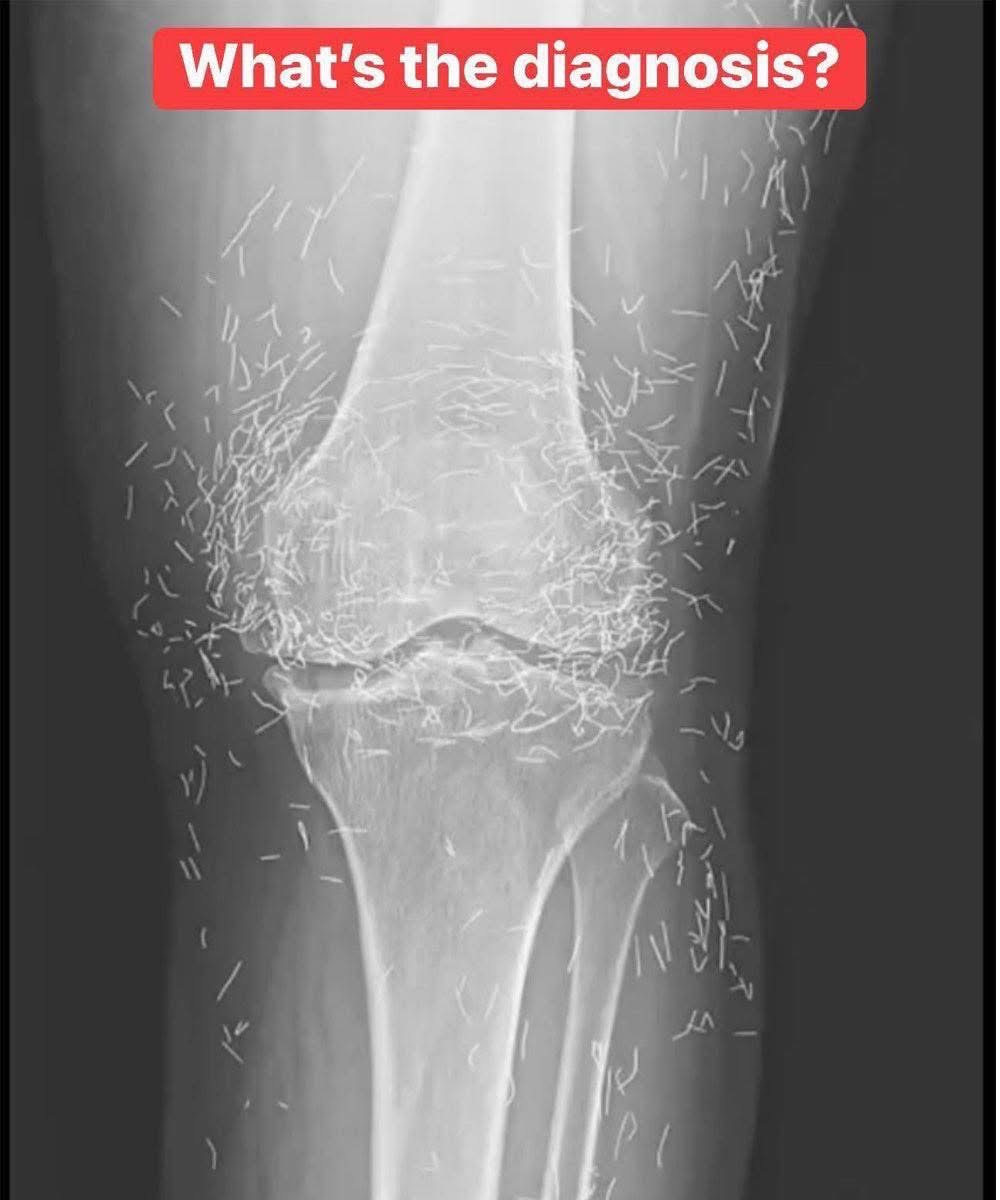

X-Ray Reveals Hundreds of Gold Needles in Woman’s Knees

Doctors examining a 65-year-old South Korean woman’s X-ray were shocked to find hundreds of tiny gold acupuncture needles embedded in her knees.

Suffering from osteoarthritis, she had turned to acupuncture after medications caused stomach issues.

Her practitioner had intentionally left the gold needles in her tissue for continued stimulation. However, experts warn this can cause inflammation, abscesses, infection, and interfere with imaging scans like X-rays or MRIs.